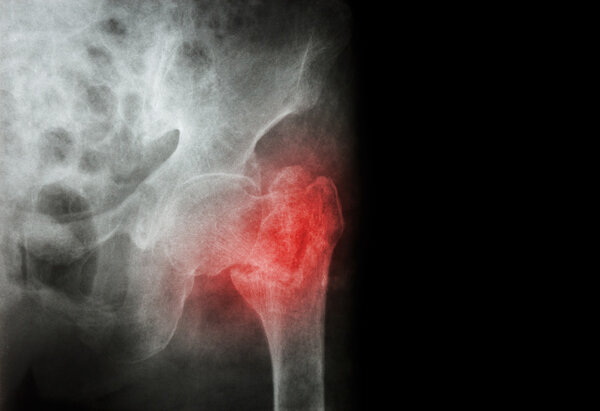

而股骨骨折,一般就是股骨遭受直接或间接暴力后,导致股骨的完整性破坏或连续性中段。最常见的原因就是暴力,比如车祸,比如滑雪摔倒,比如打架一棍子给抡骨折了,还有新闻中的这类不恰当的运动锻炼。

股骨骨折不仅可能造成患者难以言状的疼痛,严重时还可能因疼痛肿胀使患者的患肢完全丧失活动能力、出血过多休克从而危机生命安全。

股骨骨折以后,绝大多数情况下都需要手术,就像杨女士一样需要置入髓内钉,而且以后还得取出来。